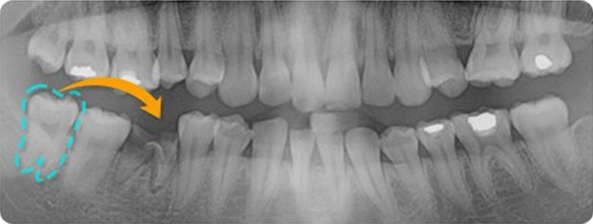

STEP 1

금이 가서 뺄 치아

STEP 2

옮겨 심게 될 사랑니

STEP 3

치아를 빼고 난 자리에 옮겨진 사랑니